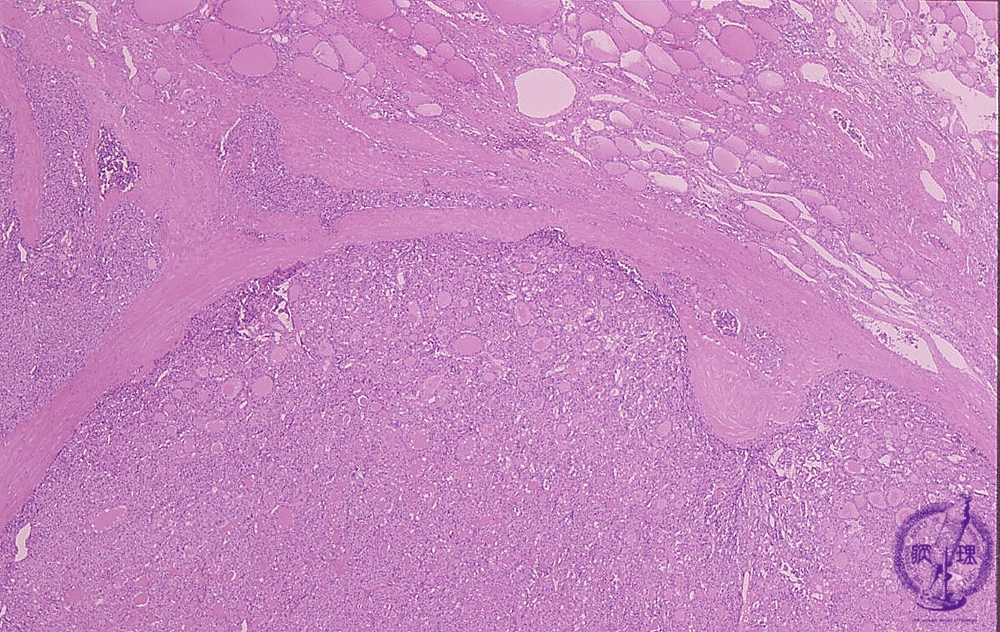

- (9)Follicular carcinoma of the thyroid

Microscopic findings (HE stain, low power view). Thyroid tumor with fibrous capsule. The presence of a tumor nest (arrows) outside the capsule is suggestive of capsular invasion.